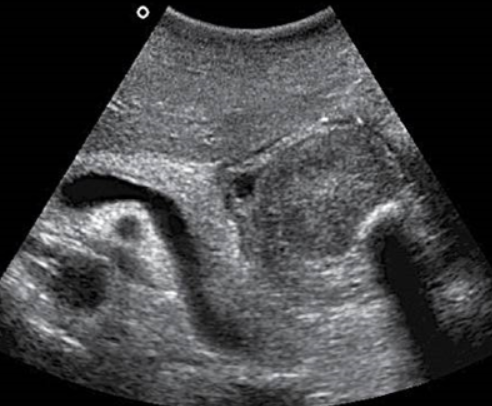

Fluid filled cecum